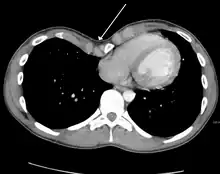

Many scales have been developed to determine the degree of deformity in the chest wall. Most of these are variants on the distance between the sternum and the spine. One such index is the Backer ratio which grades severity of deformity based on the ratio between the diameter of the vertebral body nearest to xiphosternal junction and the distance between the xiphosternal junction and the nearest vertebral body.[17] More recently the Haller index has been used based on CT scan measurements. An index over 3.25 is often defined as severe.[18] The Haller index is the ratio between the horizontal distance of the inside of the ribcage and the shortest distance between the vertebrae and sternum.[19]

Chest x-rays are also useful in the diagnosis. The chest x-ray in pectus excavatum can show an opacity in the right lung area that can be mistaken for an infiltrate (such as that seen with pneumonia).[20] Some studies also suggest that the Haller index can be calculated based on chest x-ray as opposed to CT scanning in individuals who have no limitation in their function.[21]

Treatment

Pectus excavatum requires no corrective procedures in mild cases.[22] Treatment of severe cases can involve either invasive or non-invasive techniques or a combination of both. Before an operation proceeds several tests are usually performed. These include, but are not limited to, a CT scan, pulmonary function tests, and cardiology exams (such as auscultation and ECGs).[23] After a CT scan is taken, the Haller index is measured. The patient's Haller is calculated by obtaining the ratio of the transverse diameter (the horizontal distance of the inside of the ribcage) and the anteroposterior diameter (the shortest distance between the vertebrae and sternum).[24] A Haller Index of greater than 3.25 is generally considered severe, while normal chest has an index of 2.5.[19][25][26] The cardiopulmonary tests are used to determine the lung capacity and to check for heart murmurs.[27]